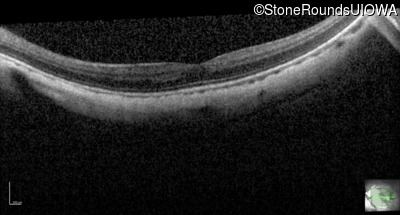

AR CSNB, normal fundus (IA2fiii)

Age at visit: 16 years

This 16 year old male has had poorer vision in dim light than his siblings since childhood. He has also been very myopic since childhood and is currently wearing -14.00 diopter spectacles. The maximum combined response of the electroretinogram reveals a selective loss of the b-wave.